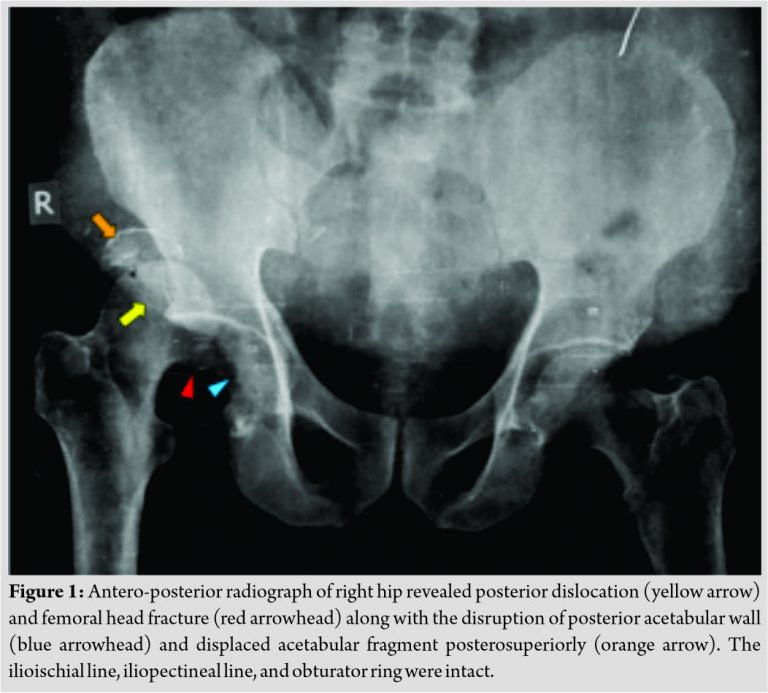

In 2015, a 60 years old male patient presented to the hospital with complaints of pain and swelling in right hip region and inability to bear weight on right lower limb for 15 days. Patient had history of motor vehicle accident and sustained injury to the right hip region. He had not taken any treatment previously and presented to us for the 1st time. On clinical examination, right lower limb was adducted and internally rotated. Movements at right hip joint were painful and restricted. Swelling was present in right gluteal region and vascular sign of Narath was positive. Distal neurovascular structures were intact. Radiograph of right hip revealed posterior dislocation and femoral head fracture with a large intra-articular fragment. There was disruption of posterior acetabular wall with a displaced acetabular fragment posterosuperiorly. The ilioischial and iliopectineal lines were intact as was the obturator ring. The femoral neck was also intact (Fig. 1).